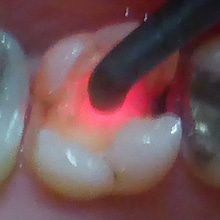

そこで、レーザーを当てて調べます。

歯にはまったくダメージは与えません。

最大54の値が出ました。

茶色部分も大きな虫歯です。

これ以上削ると神経が出てしまいますので、

歯を削らない、虫歯治療である

ドックベスト療法を行いました。